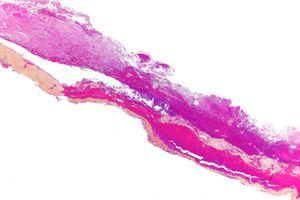

النزف تحت الجافية subdural hematoma، هو نزف يتجمع فيه الدم بين الجافية والدماغ. وهو أكثر شيوعاً من النزف فوق الجافية بنحو 10 مرات. ويحدث عادة عندما يؤدي رضّ دماغي إلى تمزق أحد (أو بعض) الأوردة التي تعبر الفراغ تحت الجافية. ومن العوامل المؤهبة لحدوث هذا النوع من النزف وجود ضمور دماغي أو انخفاض الضغط داخل القحف (إذ تؤدي هاتان الحالتان إلى تمطط الأوردة في الفراغ تحت الجافية مما يجعلها أكثر عرضة للتمزق)، ومن العوامل الأخرى اضطرابات التخثر والكحولية.

يعتمد رئيساً على تصوير الدماغ (التصوير الطبقي المحوري والرنين المغنطيسي MRI)، وفيه يظهر النزف عادة على شكل تجمع هلالي بين الجمجمة والدماغ.